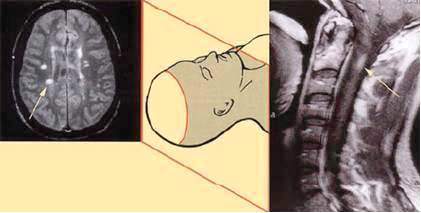

Bitna je u dijagnostici multiple skleroze, jer se njome mogu otkriti promjene

(lezije) u mozgu ili kičmenoj moždini koje upućuju na multiplu

sklerozu, a vide se kao bijela okruglasta do ovalna područja u normalno

sivom prikazu mozga ili kičmene moždine.

Te bjelkaste promjene, koje nazivamo oštećenjima ili lezijama, zapravo

najčešće prikazuju vodu koja je prodrla u područje oštećene ovojnice.

Ovojnica je hidrofobna, pa njenim oštećenjem nervno tkivo, koje je hidrofilno,

Demijelinizacijska oštećenja u multiploj sklerozi nisu podjednako raspoređena

u svim dijelovima centralnog nervnog sistema. Ona su naročito česta u

području oko moždanih komora, u dijelu mozga koji se spušta prema kičmenoj

moždini, a naziva se moždano stablo, u malom mozgu, često i u očnom nervu,

te vratnoj kičmenoj moždini. Postoji pretpostavka da su demijelinizacijska

oštećenja lokalizovana na pomenutim mjestima zbog imunološki ili hemijski

drugačije mijelinske ovojnice. Zbog navedenog razloga uvijek treba snimati

MR mozga i vratne kičme, a kod bolesnika koji imaju simptome koji odgovaraju

grudnoj kičmenoj moždini, nužno je obaviti i snimanje tog dijela kičme.

Slika MR-a mozga i vratne kičme

– demijelinizacijska oštećenja označena strelicom.